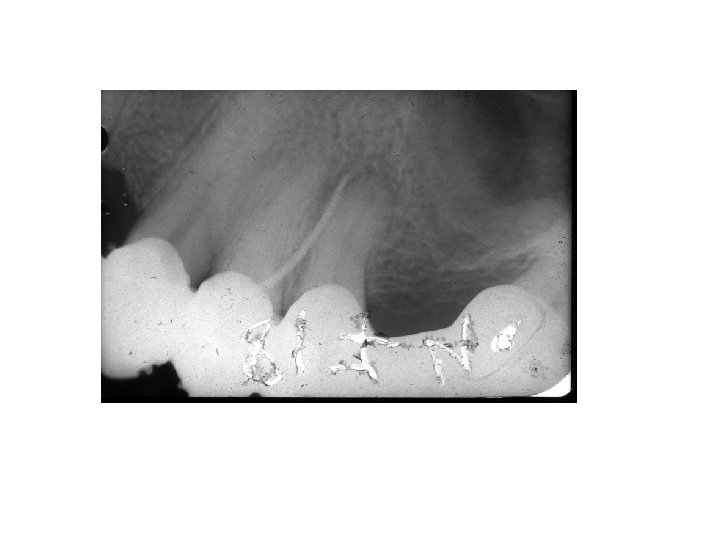

Falsch negative Diagnose • • • Foramen incisivum Foramen mentale Sinus maxillaris Foramen nasale Tuberkel von Pulpa